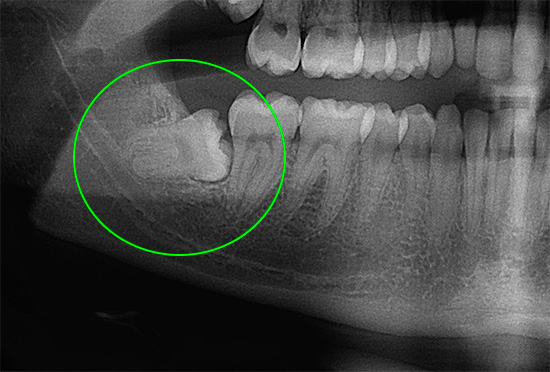

- Quando um dente do siso ou outro dente é cortado em uma criança (no entanto, os dentes do siso também não são tão simples - geralmente os dentes do siso inferiores, sem tratamento oportuno, começam a surgir com patologias que requerem intervenção cirúrgica. Não é por acaso que uma erupção dolorosa tenha um nome especial - pericoronite);

- A pulpite, que se manifesta com dor de dente grave, geralmente piora à noite. Se, neste caso, você tentar ser tratado em casa, apenas aliviando a dor com a ajuda de comprimidos, poderá praticar periodontite, fluxo e fístulas purulentas nas gengivas. Além disso, em alguns casos, a extração dentária está longe de ser a conseqüência mais triste.

- Osteomielite odontogênica, fleuma, sepse - todas essas complicações já podem ameaçar a vida de uma pessoa.